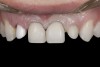

A 14-year-old patient presented to the office with his mother (Figure 1). His chief complaint involved the large spaces between the teeth created by his missing right maxillary lateral incisor and his small left maxillary lateral incisor. He desired to replace the missing tooth with an implant and create a beautiful smile. Upon examination, he was found to have a class I canine and molar relationship, but because he had a tooth size/arch size discrepancy and space distal to the right central incisor, the remaining incisors had drifted to the right. The left maxillary lateral incisor was peg-shaped and in a cross bite position. Studies have shown a clear association between congenitally missing teeth and reduced tooth size.59-62 Because he was only 14-years-old at the time and could not have implants placed until the cessation of growth (somewhere in the vicinity of 22 years old), he was sent to the orthodontist for alignment of the teeth.16,17 After 2 years of orthodontics, the appliances were removed, and his tooth coloration was improved using carbamide peroxide bleaching (Figure 2). Because some form of provisional needed to be placed until he was finished growing, a double-wing metal resin-bonded bridge was chosen. As discussed earlier, this is the ideal transitional prosthesis for patients that have congenitally missing maxillary lateral incisors. The benefits of this type of prosthesis include its ability to be removed and rebonded during the surgical phase of treatment and its ability to retain the roots in their proper position after orthodontic treatment.16 The final plan for the patient was to increase the width of the central and the maxillary left lateral incisor, utilizing porcelain laminate veneers to achieve the appropriate width/length ratio of 80%. A wax-up was created to idealize tooth size, a putty matrix was made from the wax-up to facilitate bonding of the incisors, and a non-precious, double-wing metal resin-bonded bridge was fabricated for lateral incisor replacement. Once the teeth were bonded to ideal size, the “Maryland Bridge” was fabricated from a polyvinyl arch impression with the newly bonded teeth (Figure 3). The metal frame was cast from a non-precious alloy to allow for fabrication of a very thin frame and to create a better surface for bonding. After sandblasting the internal aspect of the frame with CoJet™ silica (3M ESPE), accomplishing salinization, and executing cementation with a dual-cure resin cement, a fairly good adhesion to the frame was anticipated.29 The enamel surface was etched with phosphoric acid for 30 seconds, the primer (Single Bond Plus, 3M ESPE) was applied to both the internal surface of the sandblasted framework and the etched enamel, and the bridge was cemented with RelyX™ ARC (3M Espe) dual-cured resin cement (Figure 4 and Figure 5).

(1.) Initial presentation. Note midline shift to right, missing right lateral incisor, and diminutive left lateral incisor in crossbite.

Figure 1

(2.) After orthodontic alignment of teeth and bleaching. Note alveolar deficiency in right lateral incisor site and diminutive left lateral incisor.

Figure 2